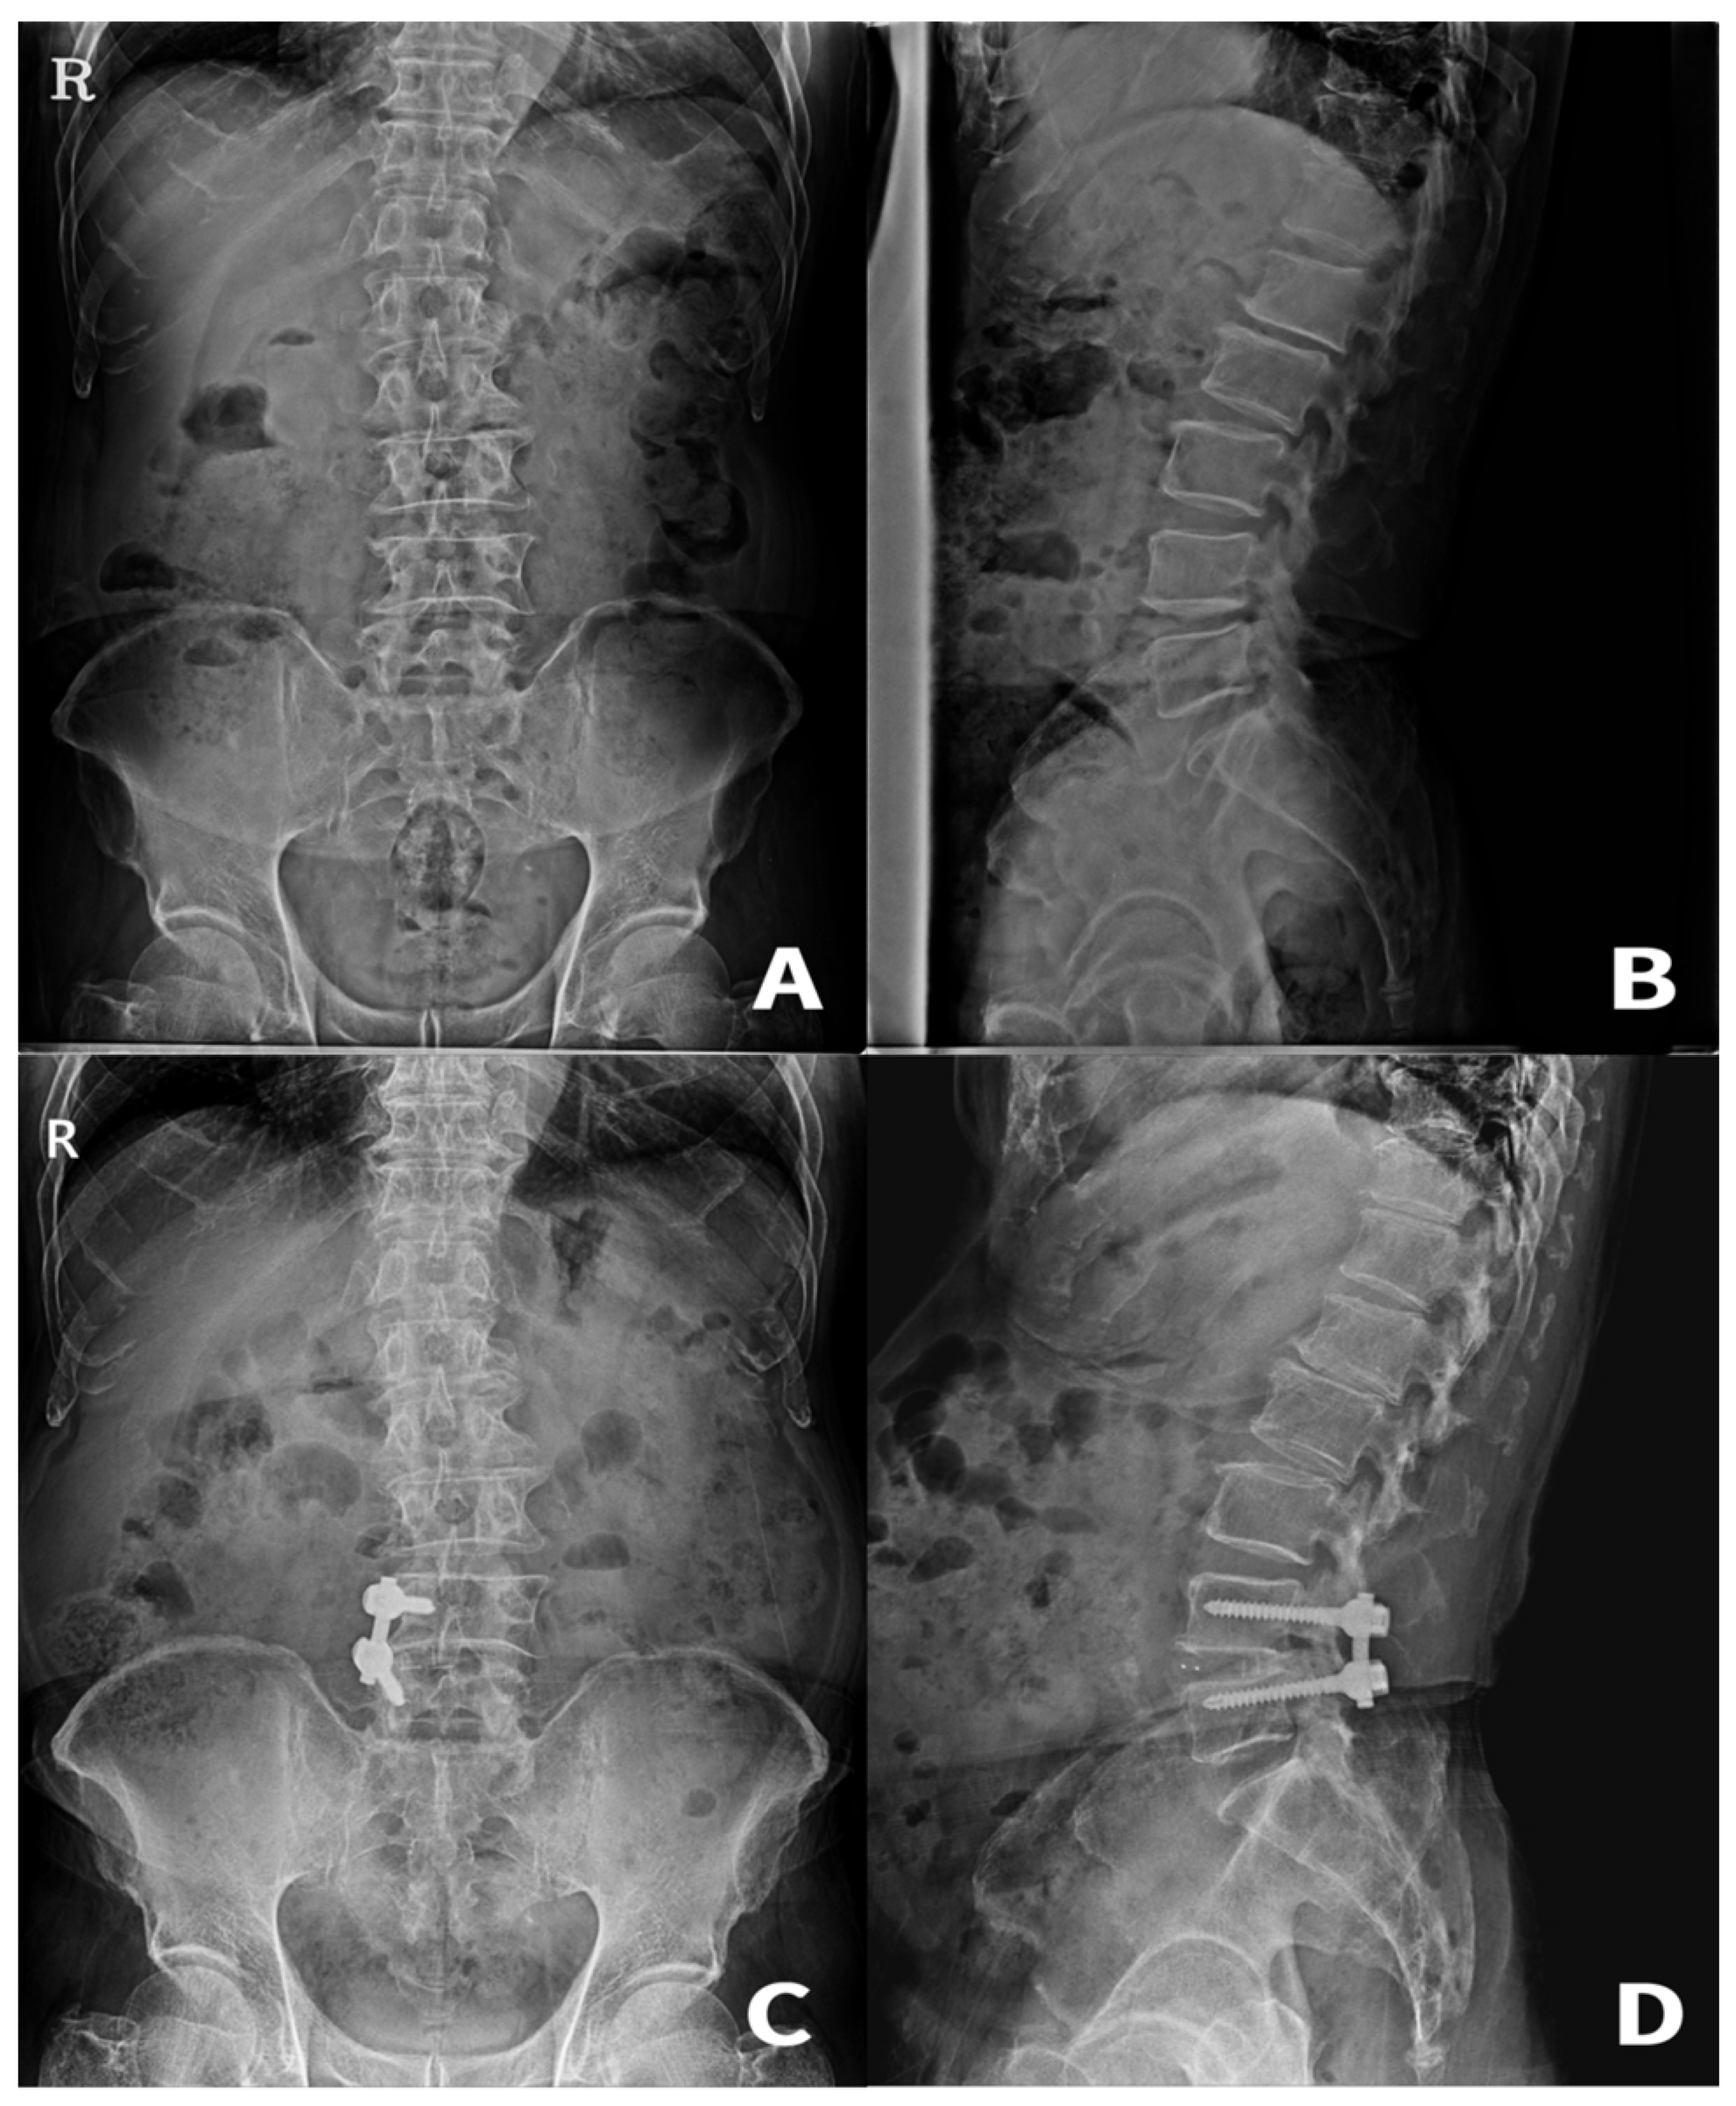

2.2. Surgical Procedures